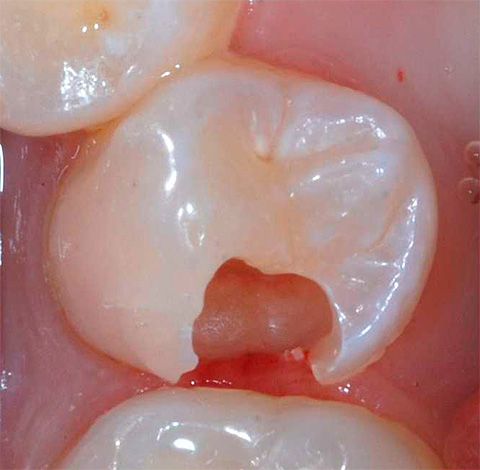

Se la carie dentaria ha raggiunto la dentina del dente, significa che hai già perso il momento in cui il trattamento dei cambiamenti patologici potrebbe essere eseguito senza l'uso di un trapano. In questa fase, una visita da un medico di solito non è completa senza perforare i denti e installare otturazioni.

All'appuntamento dentale verranno prese misure per preservare non solo il dente, ma anche la polpa ("nervo") all'interno delle sue radici. Per questo, il medico condurrà in sequenza le seguenti fasi del trattamento:

- Anestesia adeguata in modo da non provare dolore;

- Elaborazione del dente da tessuti cariati e infetti (usando un trapano);

- Lavare la cavità formata con soluzioni antisettiche;

- L'impostazione di rivestimenti e sigilli di quel livello di prezzo, che sarà negoziato in anticipo.

Va notato che attualmente producono materiali di riempimento moderni che consentono una delicata lavorazione dei denti senza eccedere i tessuti sani, a differenza dei materiali di riempimento sovietici (cementi, amalgame, ecc.). Ciò è dovuto alla possibilità che otturazioni ad alta tecnologia entrino in legami chimici con i tessuti dei denti, formando composti durevoli e inestricabili grazie a speciali sistemi adesivi (o "adesivi").